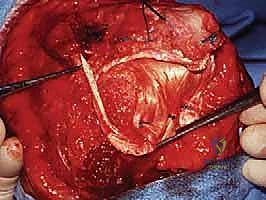

تُعد جراحة إعادة بناء الكوع من أكثر العمليات تعقيداً في تخصص العظام. يقدم الدكتور محمد هطيف مجموعة من التقنيات الجراحية المتطورة لحل أصعب المشاكل:

1. تحرير مفصل الكوع بالمنظار أو الجراحة المفتوحة (Elbow Arthrolysis)

تُستخدم هذه العملية لعلاج التيبس الشديد. يتم فيها إزالة الك